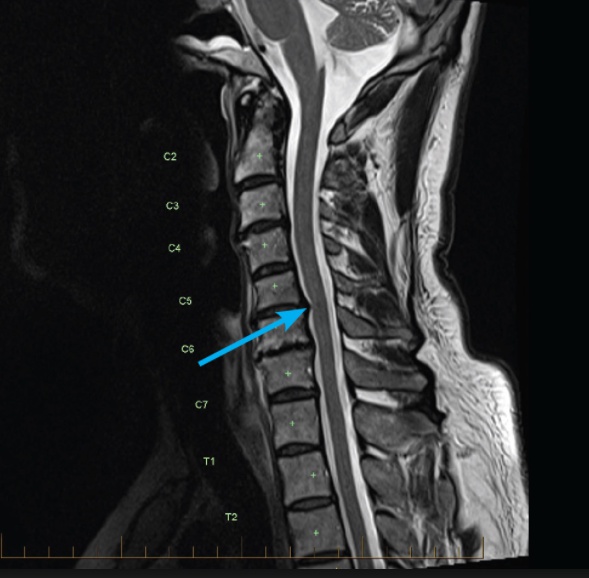

For cervical radiculopathy, imaging studies are used to confirm the diagnosis and show displacement of the CSF or compression of the nerve root. The preferred imaging studies include:

MRI as the study of choice

CT myelography is the gold standard